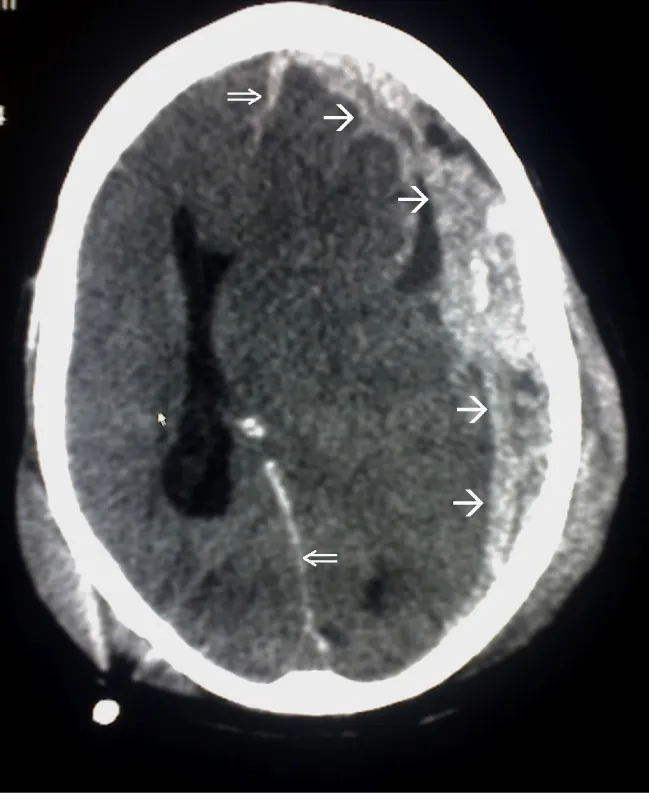

Diagnostic imaging for hemorrhagic stroke always begins with a non-contrast head CT. A head CT is the first imaging done in response to the signs and symptoms of a stroke because it determines whether a bleed is present, dictating the course of treatment. When a bleed is present, an MRI can be used to investigate further. An MRI can be useful in measuring the volume of the hematoma; differentiating between primary hemorrhage and hemorrhagic transformation of pre-existing ischemic stroke; and identifying underlying causes of the bleed, such as AVMs, tumors, and vascular disease. Serial imaging monitors for changes in hematoma and edema, as well as the possible mass effect (compression of and injury to surrounding brain tissue because of the hematoma), midline shift (a displacement of brain tissue across the midline, shown in Figure 15.9), and the development of hydrocephalus (an increase in cerebrospinal fluid in the ventricles of the brain). Computerized tomography angiography (CTA) allows for visualization of hematoma expansion and the “spot sign” that shows active contrast extravasation and indicates active hematoma expansion. Ongoing bleeding evidenced in CTA is associated with higher fatality rates (Unnithan et al., 2023).

A CT image showing a midline shift due to a hematoma.

Figure 15.9 This CT image shows a midline shift (double arrows) due to a hematoma (single arrows). The brain tissue has been displaced so that the center, or midline, of the brain is no longer in the middle. (credit: Trauma subdural arrows by Glitzy queen00/Wikimedia Commons, Public Domain)